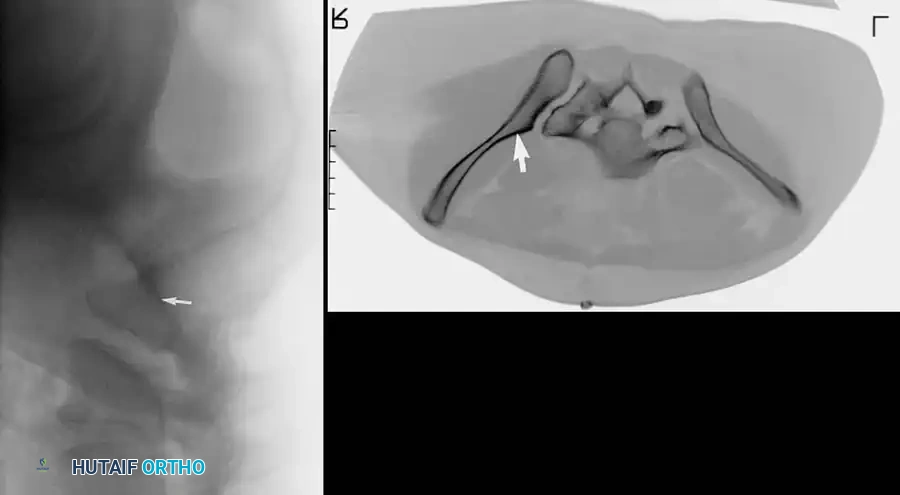

3. Percutaneous Sacroiliac (SI) Screws (Posterior Ring)

The gold standard for posterior ring fixation in appropriately selected patients.

* Indications: Sacral fractures, SI joint disruptions, crescent fractures.

* Technique: Performed under strict fluoroscopic guidance (Inlet, Outlet, and Lateral sacral views).

* Trajectory: The guide wire is advanced from the lateral ilium, across the SI joint, into the S1 (or S2) vertebral body.

* Safety Corridors: The surgeon must possess an intimate understanding of sacral dysmorphism. The "safe zone" is bounded by the sacral neural foramina inferiorly, the spinal canal posteriorly, and the sacral ala anteriorly.

Pitfall: Failure to recognize a dysmorphic sacrum (characterized by upper sacral segment elevation, non-recessed alae, and oblique neural foramina) can lead to catastrophic L5 nerve root injury or vascular penetration during SI screw placement.

Intraoperative Fluoroscopy and Reduction Techniques

Image